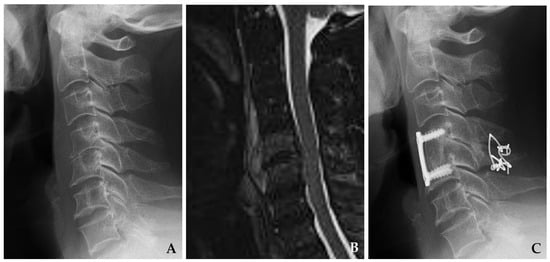

Indicated for anterior abscesses, multilevel involvement, or vertebral body destruction. Enables wide decompression and realignment, though associated with higher technical complexity and graft-related complications (Figure 4) [32,33].

Figure 4. Initial magnetic resonance imaging (A) demonstrates disc space narrowing at C5–C6 and destructive changes in the C6 vertebral body with retropharyngeal and epidural abscesses. The patient underwent C5–C7 corpectomy with autograft and anterior plating (B), achieving solid fusion and complete resolution of spondylodiscitis at six months postoperatively.